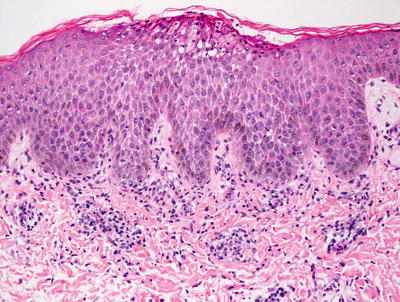

3.7.2 Histology

Histologic sections demonstrate skin with subcorneal abscesses containing a predominance of eosinophils (Fig. 3.15). Parakeratosis is variably present depending upon the age of the lesion. Within the dermis, there is a relatively slight inflammatory infiltrate that consists of lymphocytes, histiocytes, and scattered eosinophils. Increased numbers of Langerhans cells are also present within lesions [50].

Fig. 3.15

Erythema toxicum neonatorum shows a subcorneal eosinophilic abscess